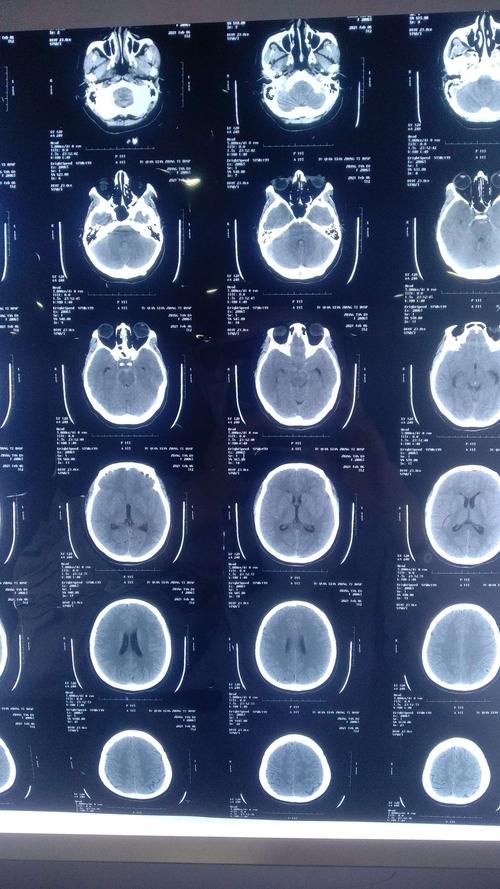

蛛网膜下腔出血图片,蛛网膜下腔出血ct

蛛网膜下腔出血ct

蛛网膜下腔出血ct表现

蛛网膜下腔出血ct解读

蛛网膜下腔出血影像图

蛛网膜下腔出血ct图解